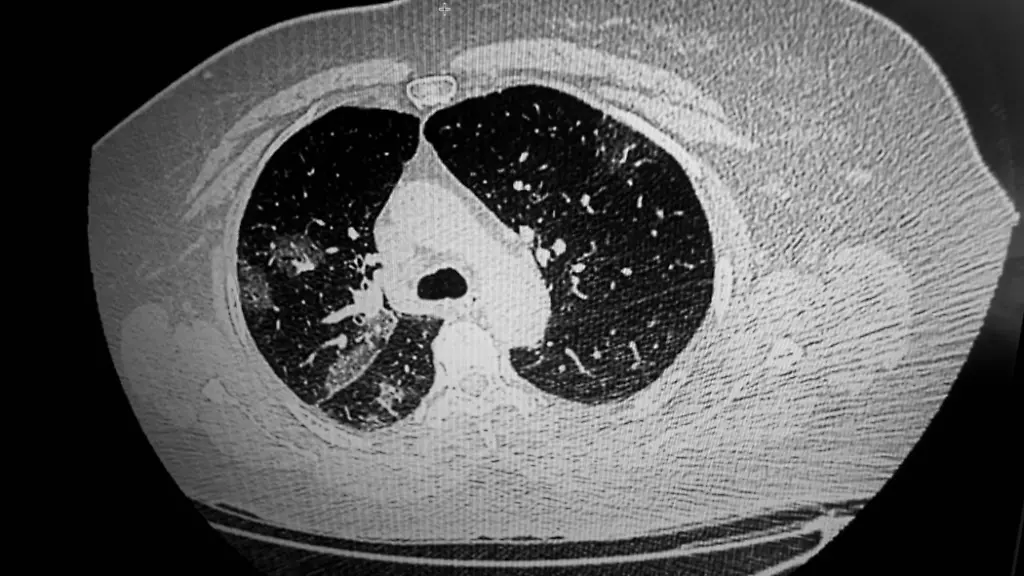

Eine gesunde Lunge sieht im CT normalerweise recht schwarz aus. Wir sehen darin lediglich viele kleine helle Punkte und Striche. Das sind die Gefäße. Wenn wir zusätzlich weißliche Areale entdecken, die zum Beispiel wie Milchglas aussehen, ist das ein Hinweis auf vermehrte lokale Flüssigkeit und damit eben auch auf einen pathologischen Prozess in der Lunge. Bei Covid-19 gibt es aber auch noch andere konkrete Hinweise.

Bei einer Covid-19-Erkrankung sehen wir in den CT-Bildern gehäuft eine Kombination pathologischer Veränderungen, die bei anderen Lungenprozessen sonst nur einzeln vorkommen. Manchmal sieht das aus wie ein Pflastersteinrelief und ein anderes Mal wie bei einem Südsee-Atoll im Meer. Obwohl wir diese Bilder auch von anderen Erkrankungen kennen, fällt bei Covid-19-Erkrankten auf, dass es den Patienten nach eigenen Angaben oft noch ganz gut geht, obwohl sie schon ein sichtbar vorangeschrittenes Geschehen in ihren Lungen haben. Selbst wenn die Sauerstoffsättigung im Blut schon nicht mehr im normalen Bereich ist, fühlen sich die Patienten subjektiv häufig noch gar nicht so schlecht. Normalerweise sieht man solche CT-Bildern nur bei schwerkranken Patienten auf der Intensivstation. Bei Covid-19 kommen die Patienten dagegen zum Teil damit noch selbständig in die Notaufnahme. Zudem gibt es schon ganz früh im Verlauf der Erkrankung im CT sichtbare Veränderungen der Lunge bei gleichzeitig vollständig fehlender pulmonaler Symptomatik.

Die Lunge reagiert immer ähnlich auf Viren oder auch auf andere schädigende Stoffe wie zum Beispiel Giftgase. Zuerst kommt es zu einer Schwellung des Lungengewebes. Die führt so weit, dass die Zellen geschädigt werden und Wasser austritt. Dieses Wasser sehen wir dann in den CT-Bildern eben als diese schon beschriebenen Milchglasfärbungen.

Das weiß man ja zu diesem Zeitpunkt noch nicht. Es gibt dazu aber mehrere Theorien. Die für mich plausibelste ist die der ACE-2-Rezeptoren, an die sich das Virus in der Zelle andockt. Diese Rezeptoren befinden sich an der Oberfläche der Zellen und sind eigentlich dafür vorgesehen, einen Botenstoff zu erzeugen, der die Lunge schützt. Durch das Andocken der Viren verliert die Lunge so die Fähigkeit, sich selbst zu schützen. Die befallenen Zellen gehen unter, es kommt zu einer entzündlichen Gewebsverdickung und zusätzlich sammelt sich vermehrt entzündliche Flüssigkeit in den Lungenbläschen. Da häufig große Teile der Lunge gleichzeitig betroffen sind, haben viele Patienten das Gefühl, innerlich zu ertrinken. In den betroffenen Lungenabschnitten kann Sauerstoff nicht mehr ausreichend ausgetauscht werden und so kommt es rasch zu ausgeprägten Atembeschwerden. Das, was sich da ausbildet, würde ich eher als Schock-Lunge bezeichnen, denn vergleichbare Bilder sehen wir beispielsweise bei Frühgeborenen, im Rahmen septischer Schocks, bei Langzeitbeatmeten auf der Intensivstation oder eben nach schweren Unfällen.

Bei Covid-19 ist das zum Teil anders als bei anderen Lungenerkrankungen. Tuberkulosebakterien zum Beispiel bevorzugen häufig gut belüftete obere Lungenabschnitte. Eine klassische Lungenentzündung durch Pneumokokken konzentriert sich dagegen meist nur auf einem Lungenlappen. Eine Infektion mit Staphylokokken oder Streptokokken bildet Herde, die sich gewöhnlich an den Rändern der Lunge zeigen. Bei Sars dagegen ist auffällig, dass die Viren alle Lungenabteilungen gleichermaßen befallen können. Das kann lokal, peripher sein oder auch diffus über die Lunge verteilt. Es zeigt sich uns ein ganz unterschiedliches Bild. Das hängt meines Erachtens damit zusammen, an welcher Stelle die Viren zuerst landen.

Ja, bei einigen Patienten sehen wir bereits zu einem Zeitpunkt Lungenveränderungen, bei dem diese als Symptome lediglich leichte Halsschmerzen und trockenen Husten aufweisen. In erster Linie handelte es sich um diffuse lokal begrenzte milchglasartige Eintrübungen. Auch wenn man einschränken muss, dass diese Veränderungen nicht ausschließlich bei Sars-CoV-2-Infizierten auftreten, ist eine Lungenbeteiligung in einem so frühen und symptomarmen Stadium doch recht ungewöhnlich und somit hochsuspekt auf das Vorliegen von Covid-19 im Vergleich zu etwa einer normalen Influenza oder anderen viralen oder bakteriellen Erkrankungen des Nasen-Rachenraums.